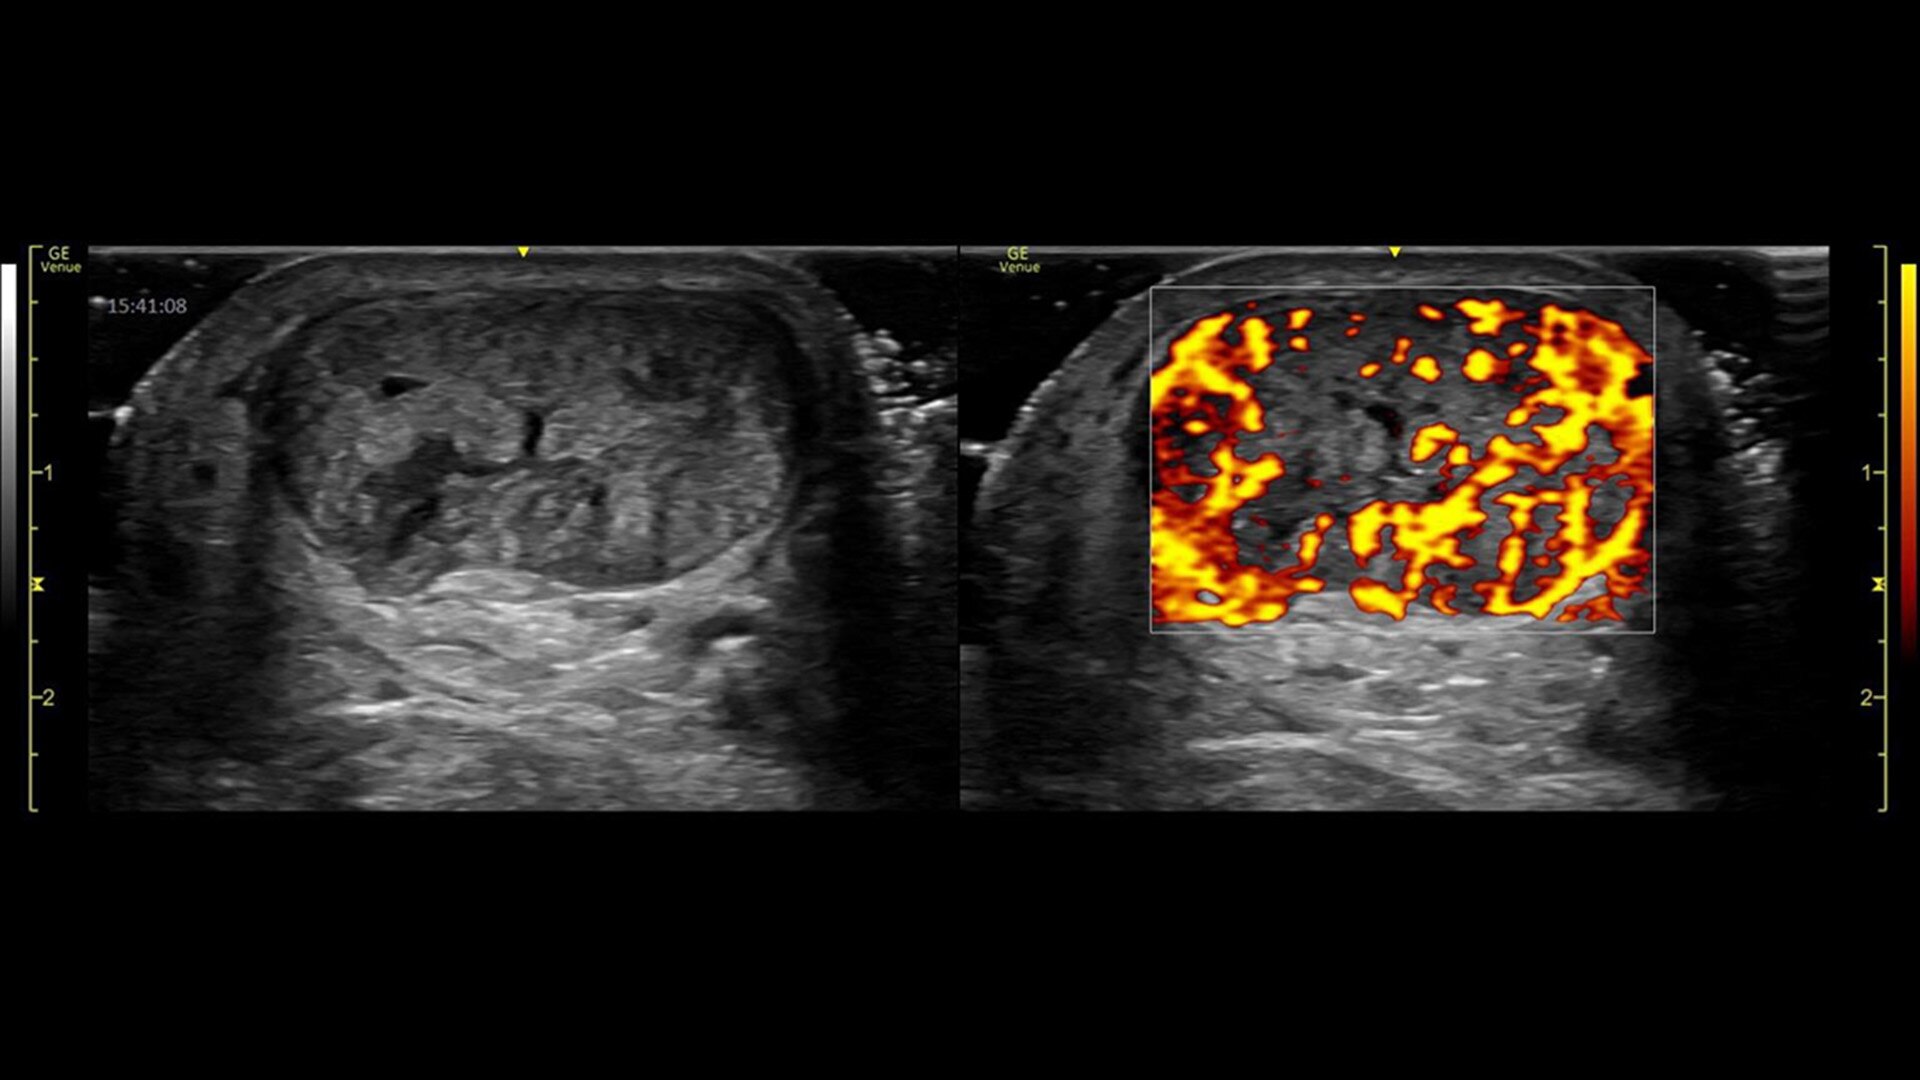

Power Doppler Imaging

Visualize slower blood flows

Power Doppler Imaging + (PDI+) is a color flow mapping technique used to map the strength of a Doppler signal coming from the flow rather than the frequency shift of the signal. In PDI+ mode, the sensitivity of the color in the Region of Interest (ROI) increases. Providing a higher resolution than the regular PDI mode, PDI+ is best used for slower blood flows such as those found in wrists, ankles, hands, and feet. This is an additional option that exists within the regular PDI mode.